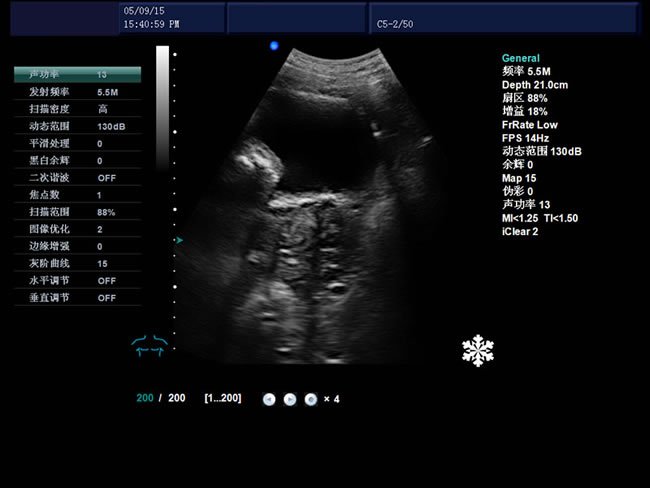

• S8彩色多普勒獸用超聲診斷儀是徐州市大為電子設(shè)備有限公司推出的一款全新的彩色超聲診斷儀器。

適用范圍:B超機(jī)產(chǎn)品性能

高集成數(shù)字式彩色多普勒技術(shù)

1、檢查母豬的空懷,降低無效飼養(yǎng)的功效早已深入人心

2、用B超監(jiān)測可及早準(zhǔn)確掌握妊娠母豬頭數(shù),較高的早期妊娠診斷準(zhǔn)確率較好的保證了均衡生產(chǎn)

3、探查時(shí)間短、無應(yīng)激、準(zhǔn)確率高,而且產(chǎn)生巨大的生產(chǎn)應(yīng)用價(jià)值